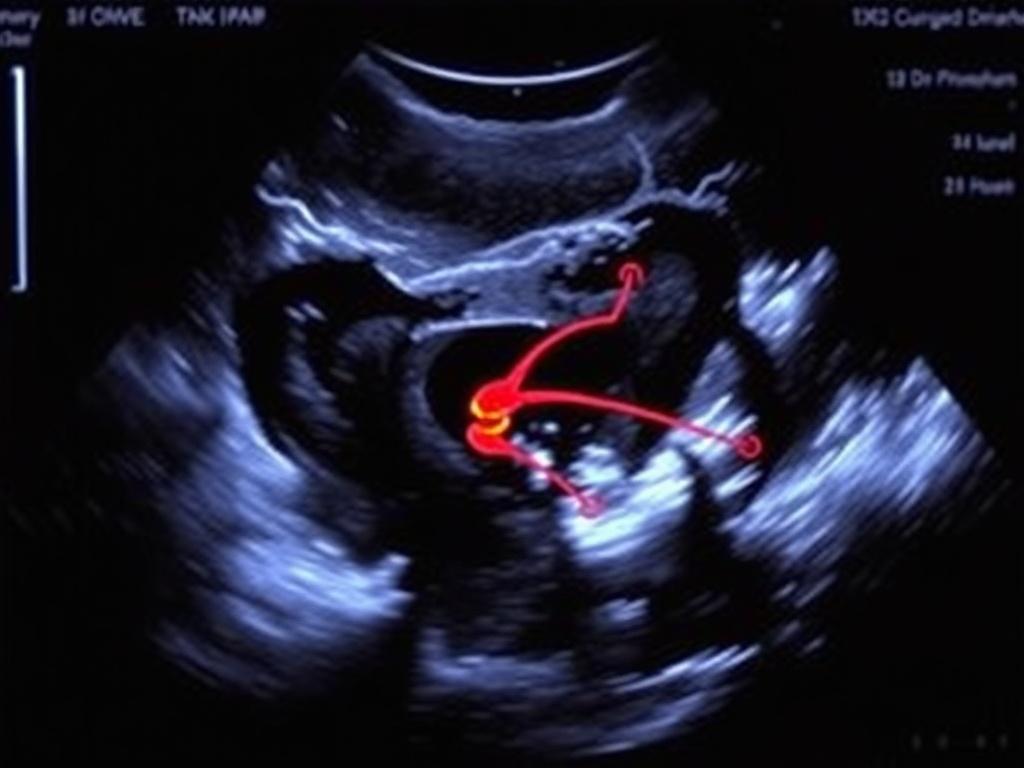

Эхокардиография — отдельный мир с собственными протоколами. Здесь ультразвук даёт оценку камер, клапанов и сократительной функции в реальном времени, что критично при bedside-диагностике.

Доплеровские методы позволяют исследовать скорость кровотока в артериях и венах, выявлять тромбозы, оценки клапанной недостаточности. Сонографическое исследование сосудов шеи дает понятные анатомические ориентиры и функциональные наблюдения.